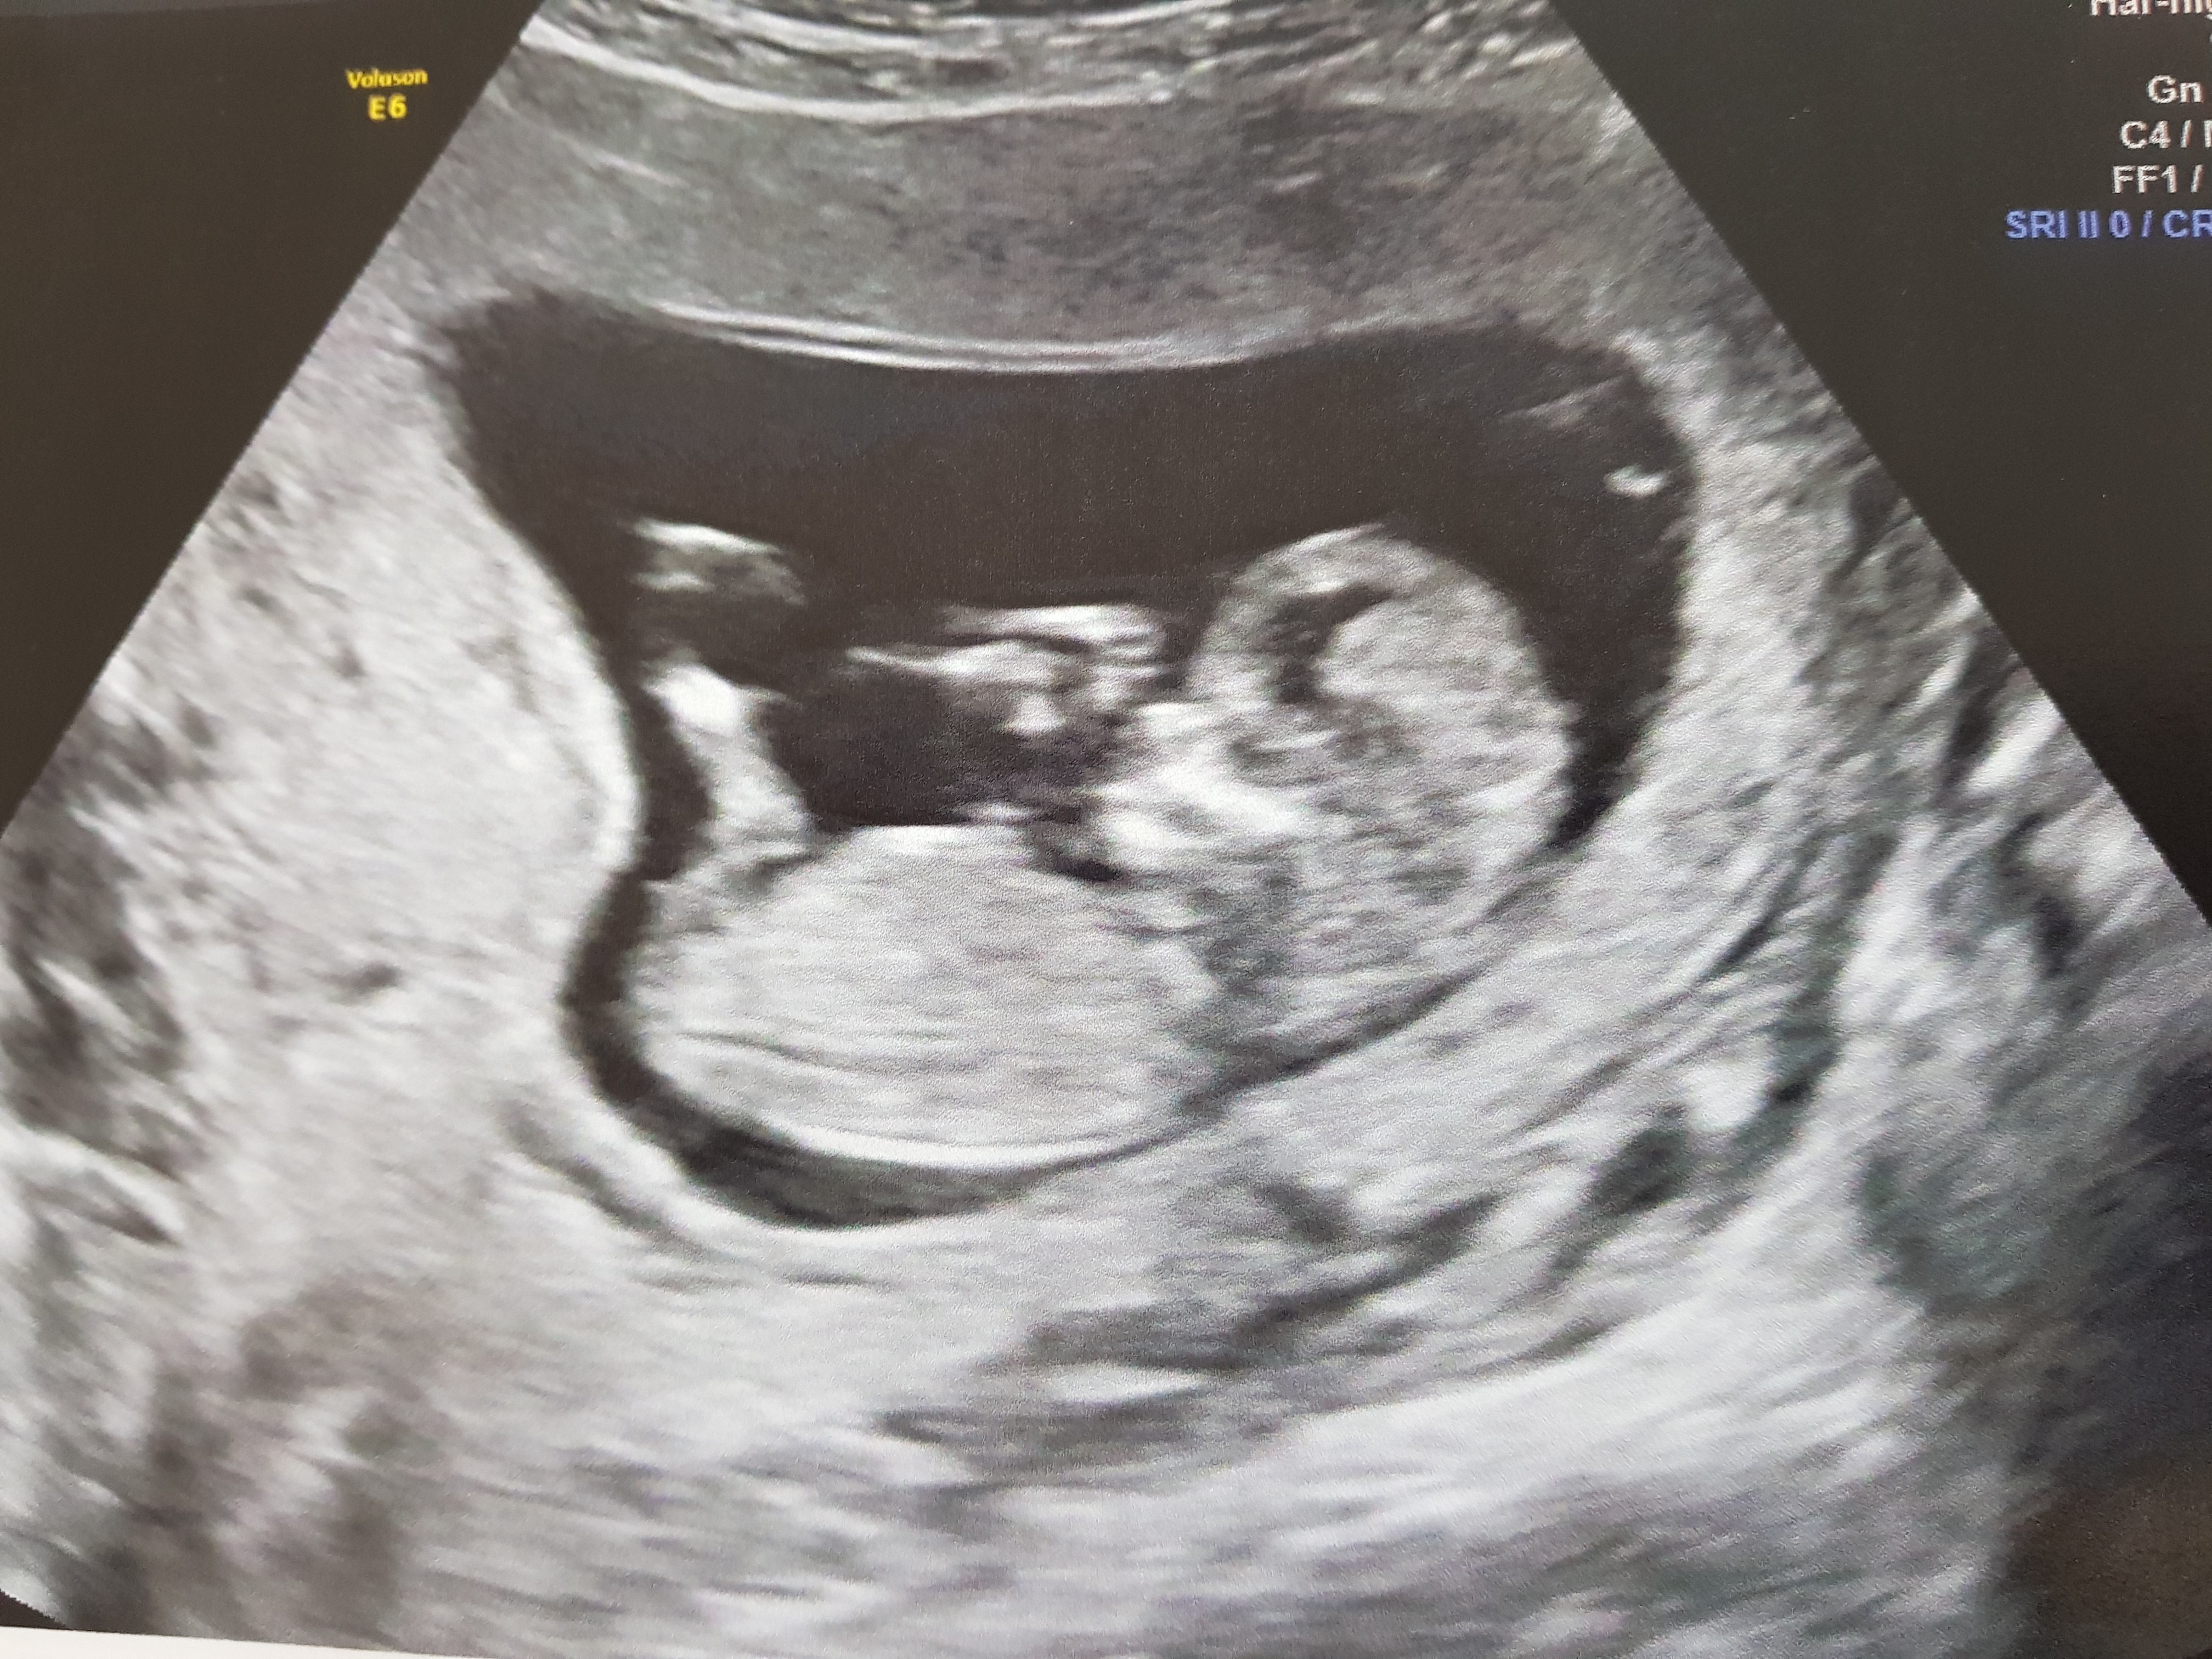

Echographie Deuxieme Trimestre L Echographie Du Deuxieme Trimestre Dite Echographie Morphologique Permet D Evaluer La Croissance Et Le Developpement Du Fœtus Tout En Faisant Une Etude Detaillee De Sa Morphologie C Est Egalement Au